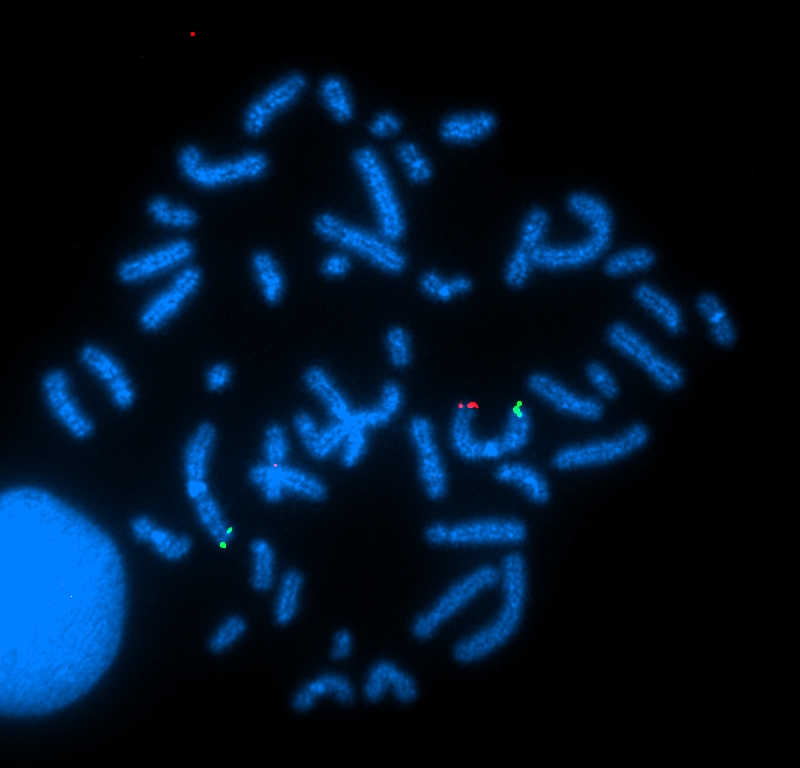

FISH Texas Red detects SKI, FITC detects D1S3739,DAPI counterstain |

|

karyotype Spectrum Green detects CEB108/T7, DAPI counterstain |